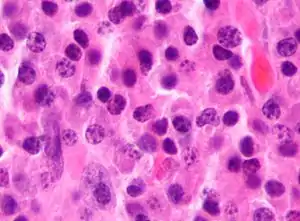

Plasmacytoma/pathology Micrograph of a plasmacytoma.

Micrograph of a plasmacytoma. Micrograph of a plasmacytoma. H&E stain.

Micrograph of a plasmacytoma. H&E stain.